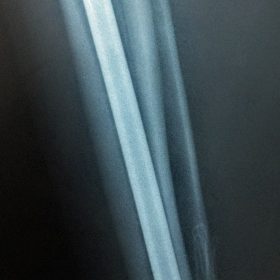

Κατάγματα Μηριαίου ή Κνήμης

Τα κατάγματα της Διάφυσης των οστών της κνήμης και του Μηριαίου οστού στη σύγχρονη ΟΡΘΡΟΠΑΙΔΙΚΗ αντιμετωπίζονται με ΕΝΔΟΜΥΕΛΙΚΗ ΗΛΩΣΗ.